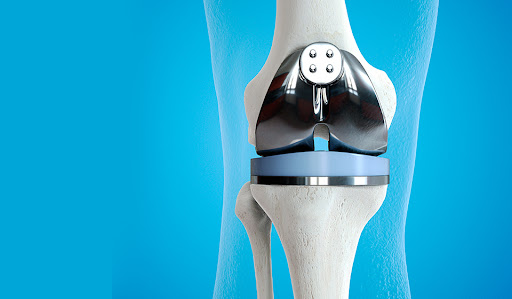

무릎 인공관절 수술은 많은 사람들이 고통받고 있는 관절 질환을 효과적으로 치료하는 방법 중 하나입니다. 이 수술을 통해 많은 환자들이 통증에서 벗어나 보다 나은 삶의 질을 누릴 수 있게 됩니다. 하지만, 수술 후 회복 과정은 개인마다 매우 다를 수 있으며, 회복 기간 동안 환자는 신체적, 정서적, 사회적 변화에 직면하게 됩니다. 이 블로그 포스트에서는 무릎 인공관절 수술 이후의 회복 기간을 단계별로 나누어 자세히 설명하고, 각 단계에서 어떤 점을 유의해야 하는지 알아보겠습니다. 따라서, 무릎 인공관절 수술을 고려하는 분들이라면 이 글이 큰 도움이 될 것입니다. 궁금한 점이 있거나 추가 정보가 필요하다면 아래의 버튼을 클릭해 주세요.